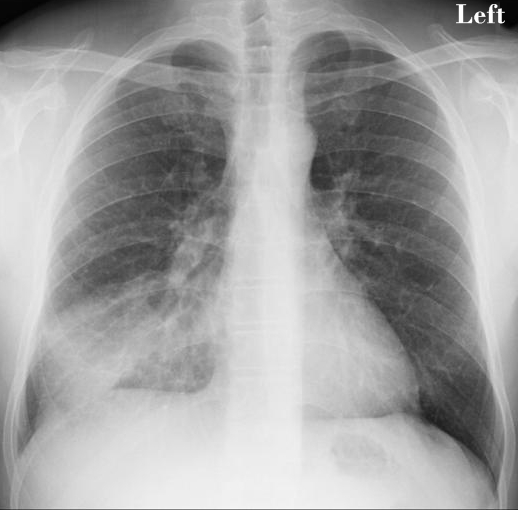

When Katherine first started to feel sick, she thought she had the flu or some other type of respiratory infection. She had a cough, trouble breathing, and chest pains. This is part of what makes mesothelioma so insidious. This is a cancer that attacks the lining of tissue around the lungs. It is most often caused by exposure to asbestos, but it does not develop into symptoms until decades after the exposure occurs.

In the meantime, people like Katherine have no idea that they are getting sick. When they do start to experience symptoms, they are often diagnosed as having an infection, pneumonia, or even lung cancer. Luckily for Katherine, although she was not diagnosed correctly right away, she still received her diagnosis when the cancer was in an early stage. Others are not so lucky and do not get an accurate diagnosis until much later.

Katherine opted for the most aggressive and riskiest treatment option, but also the one most likely to cure her cancer. As optimistic as ever, Katherine underwent an extrapleural pneumonectomy. Her surgeon removed the tissue called the pleura, in which the cancer originated, her entire right lung, and part of her diaphragm. She followed up this major and risky surgery with months of radiation treatment to try to kill every last cancer cell.